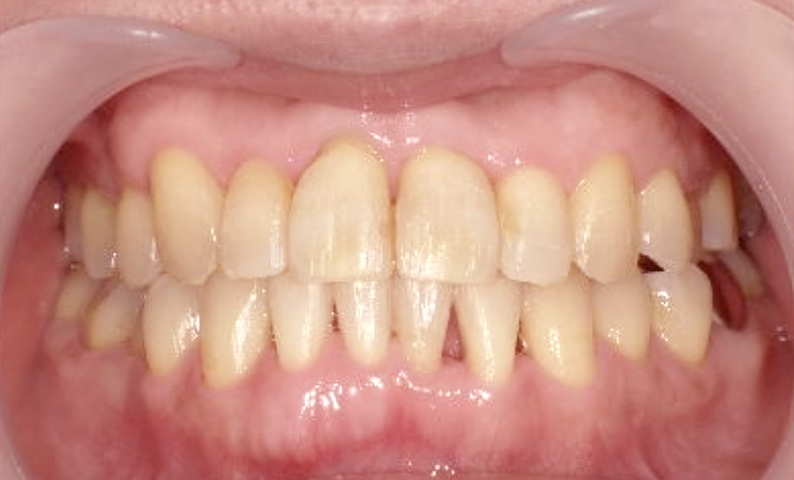

症例_003 下顎だけの部分矯正

治療期間:10ヶ月金額:24万円+税女性前歯のガタガタ下の前歯だけ上顎は補綴治療中

| Before | After |

|---|---|

|